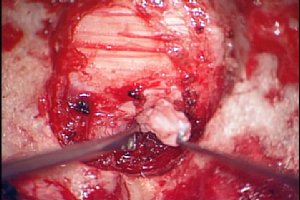

頚椎椎間板ヘルニアの顕微鏡下後方摘出術 |

ヘルニアを摘出しているところ | ||